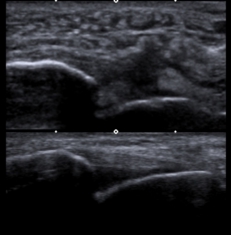

上段画像:前距腓靭帯損傷

下段画像:正常画像

と言った具合に、患者さんと一緒に超音波を見ながら、健側と比較することによって靭帯断裂を認識でき、

動かしながら評価することによって、不安定性の確認をすることができるのです。